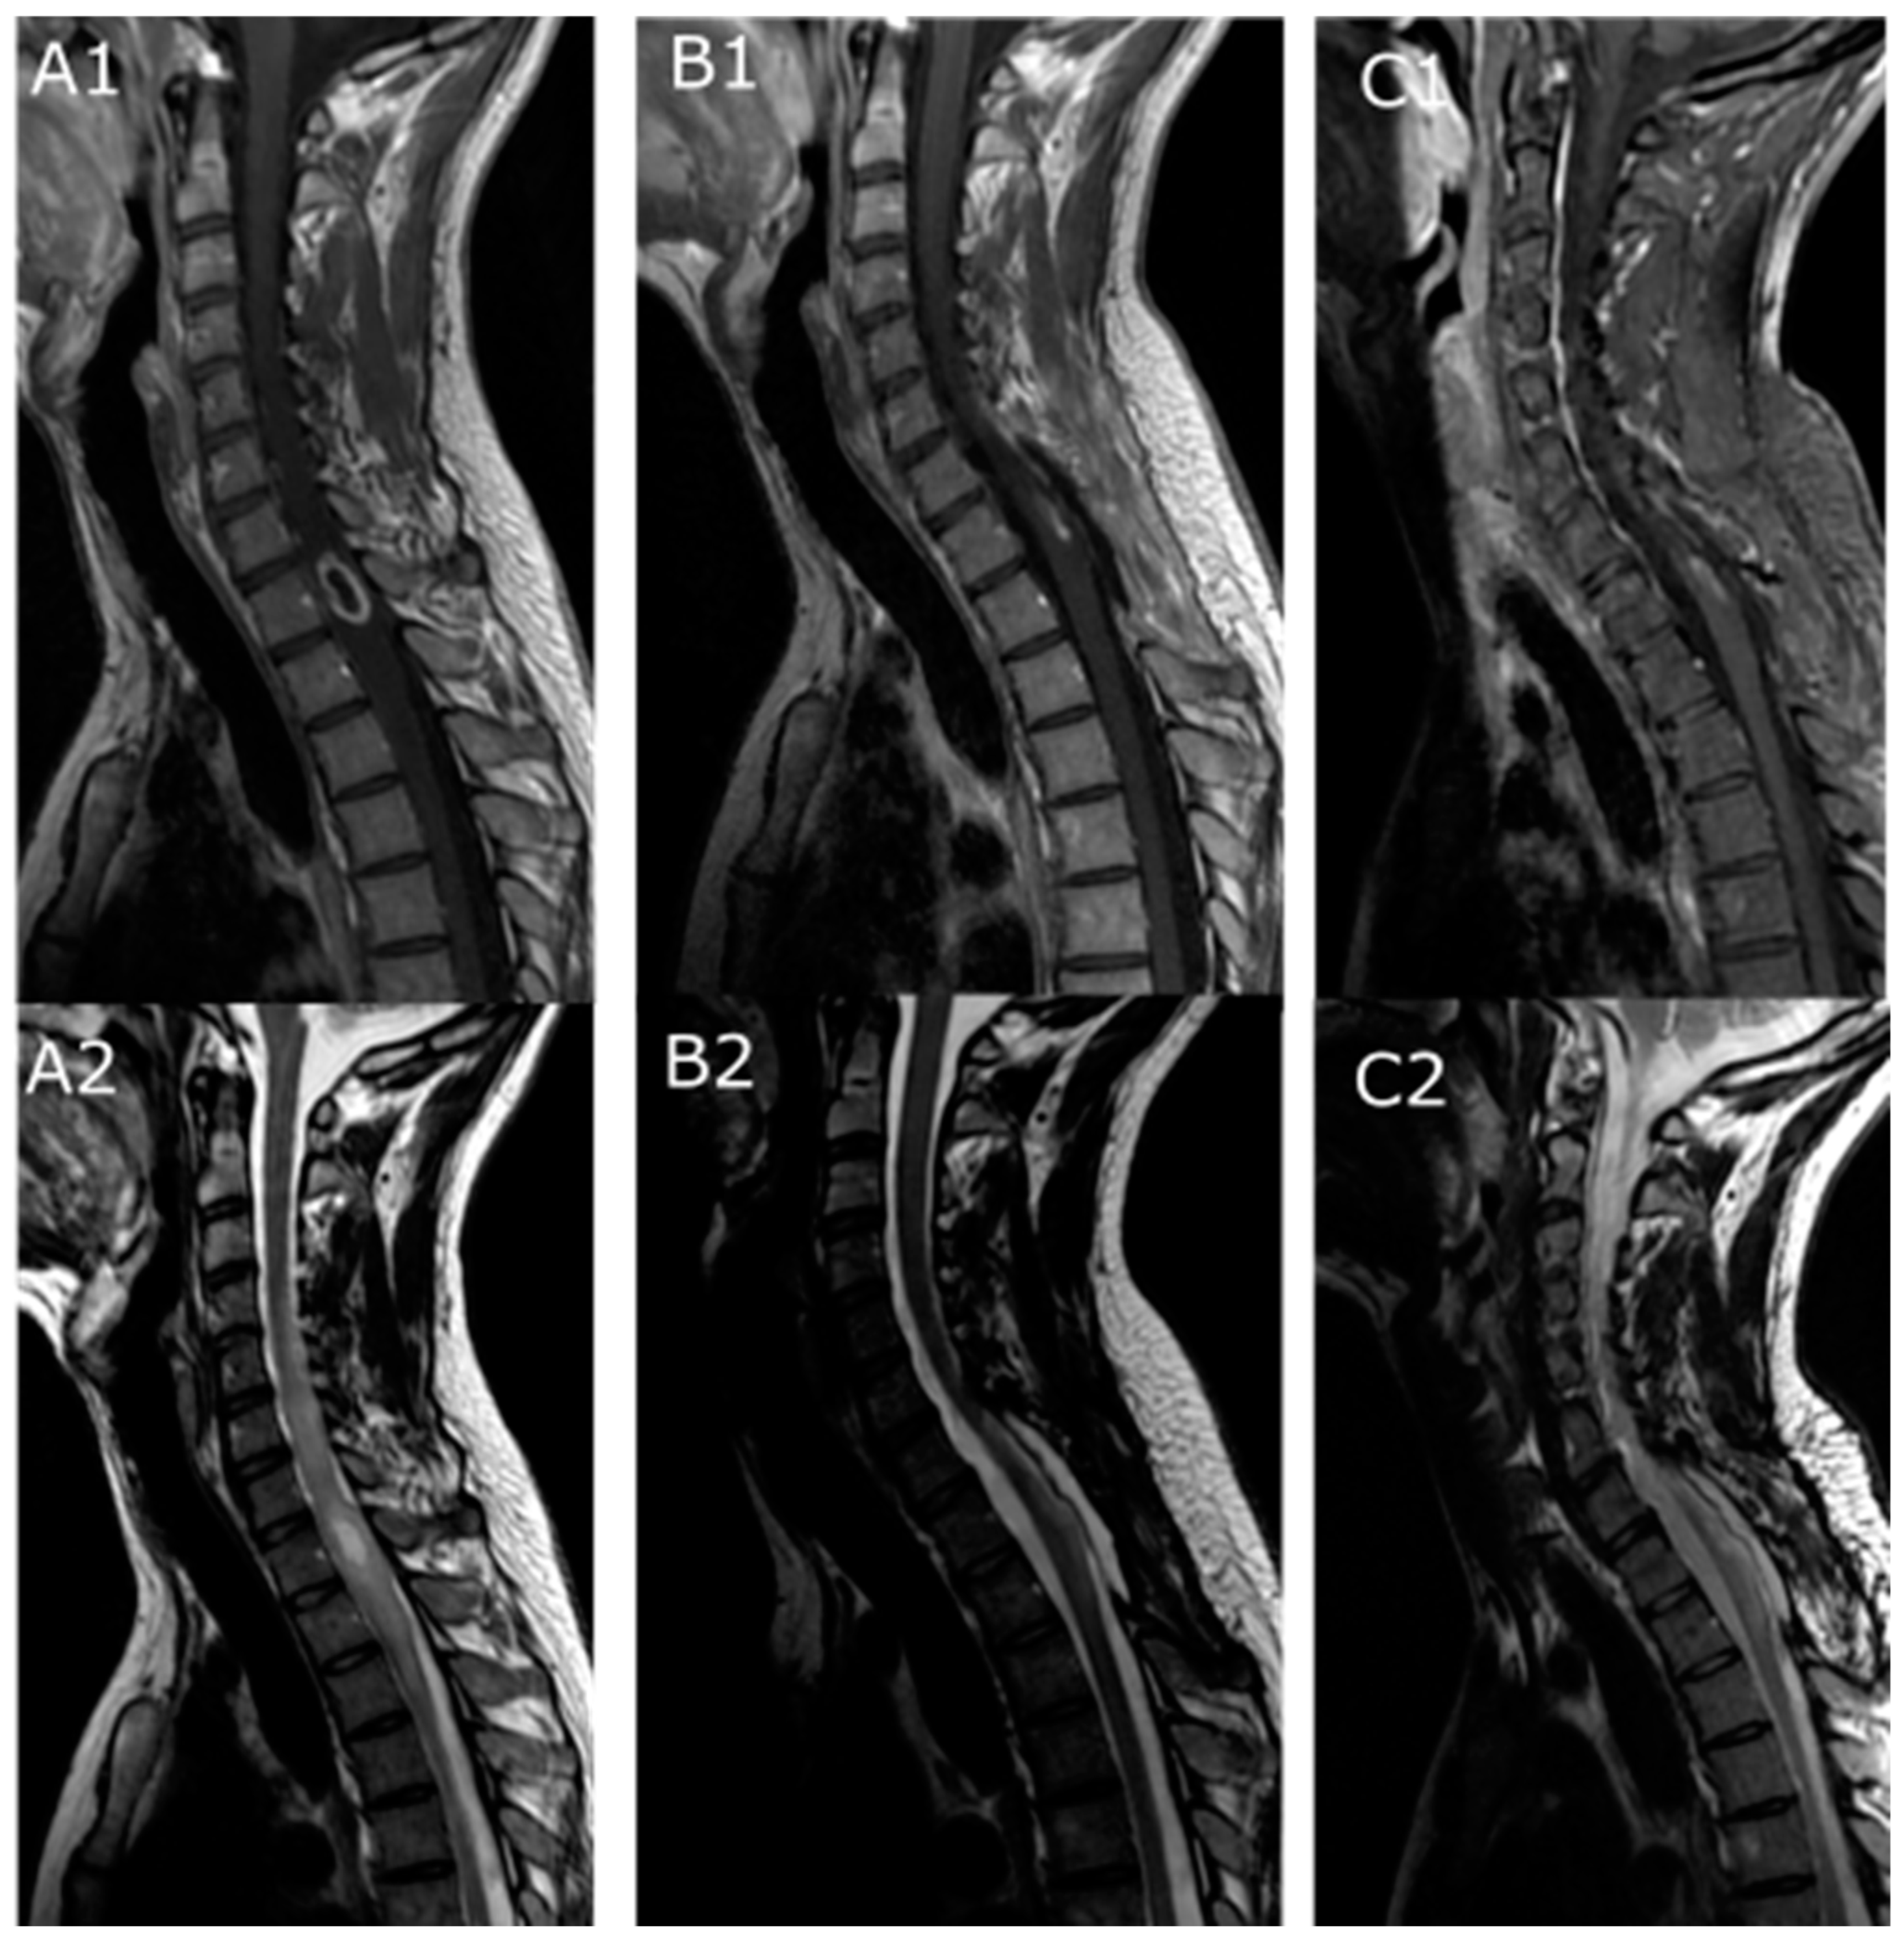

| Vertebral levels involved | Mean (min–max) | 3 (1–9) |

| Cervical | 8 (26.7%) | |

| Cervicodorsal | 2 (6.7%) | |

| Dorsal | 18 (60%) | |

| Dorsolumbar | 2 (6.7%) | |

| T1-weighted sequence signal (%) | Hypo | 11/23(47.8%) |

| Iso | 10/23 (43.5%) | |

| Hyper | 2/23 (8.7%) | |

| T2-weighted sequence signal (%) | Hypo | 2/24 (8.3%) |

| Iso | 0 | |

| Hyper | 22/24 (91.7%) | |

| Gadolinium enhancement | 26 (86.7%) | |

| Peritumoral cyst | 18/29 (62%) | |

| Peritumoral hemorrhage | 9/28 (32.1%) | |